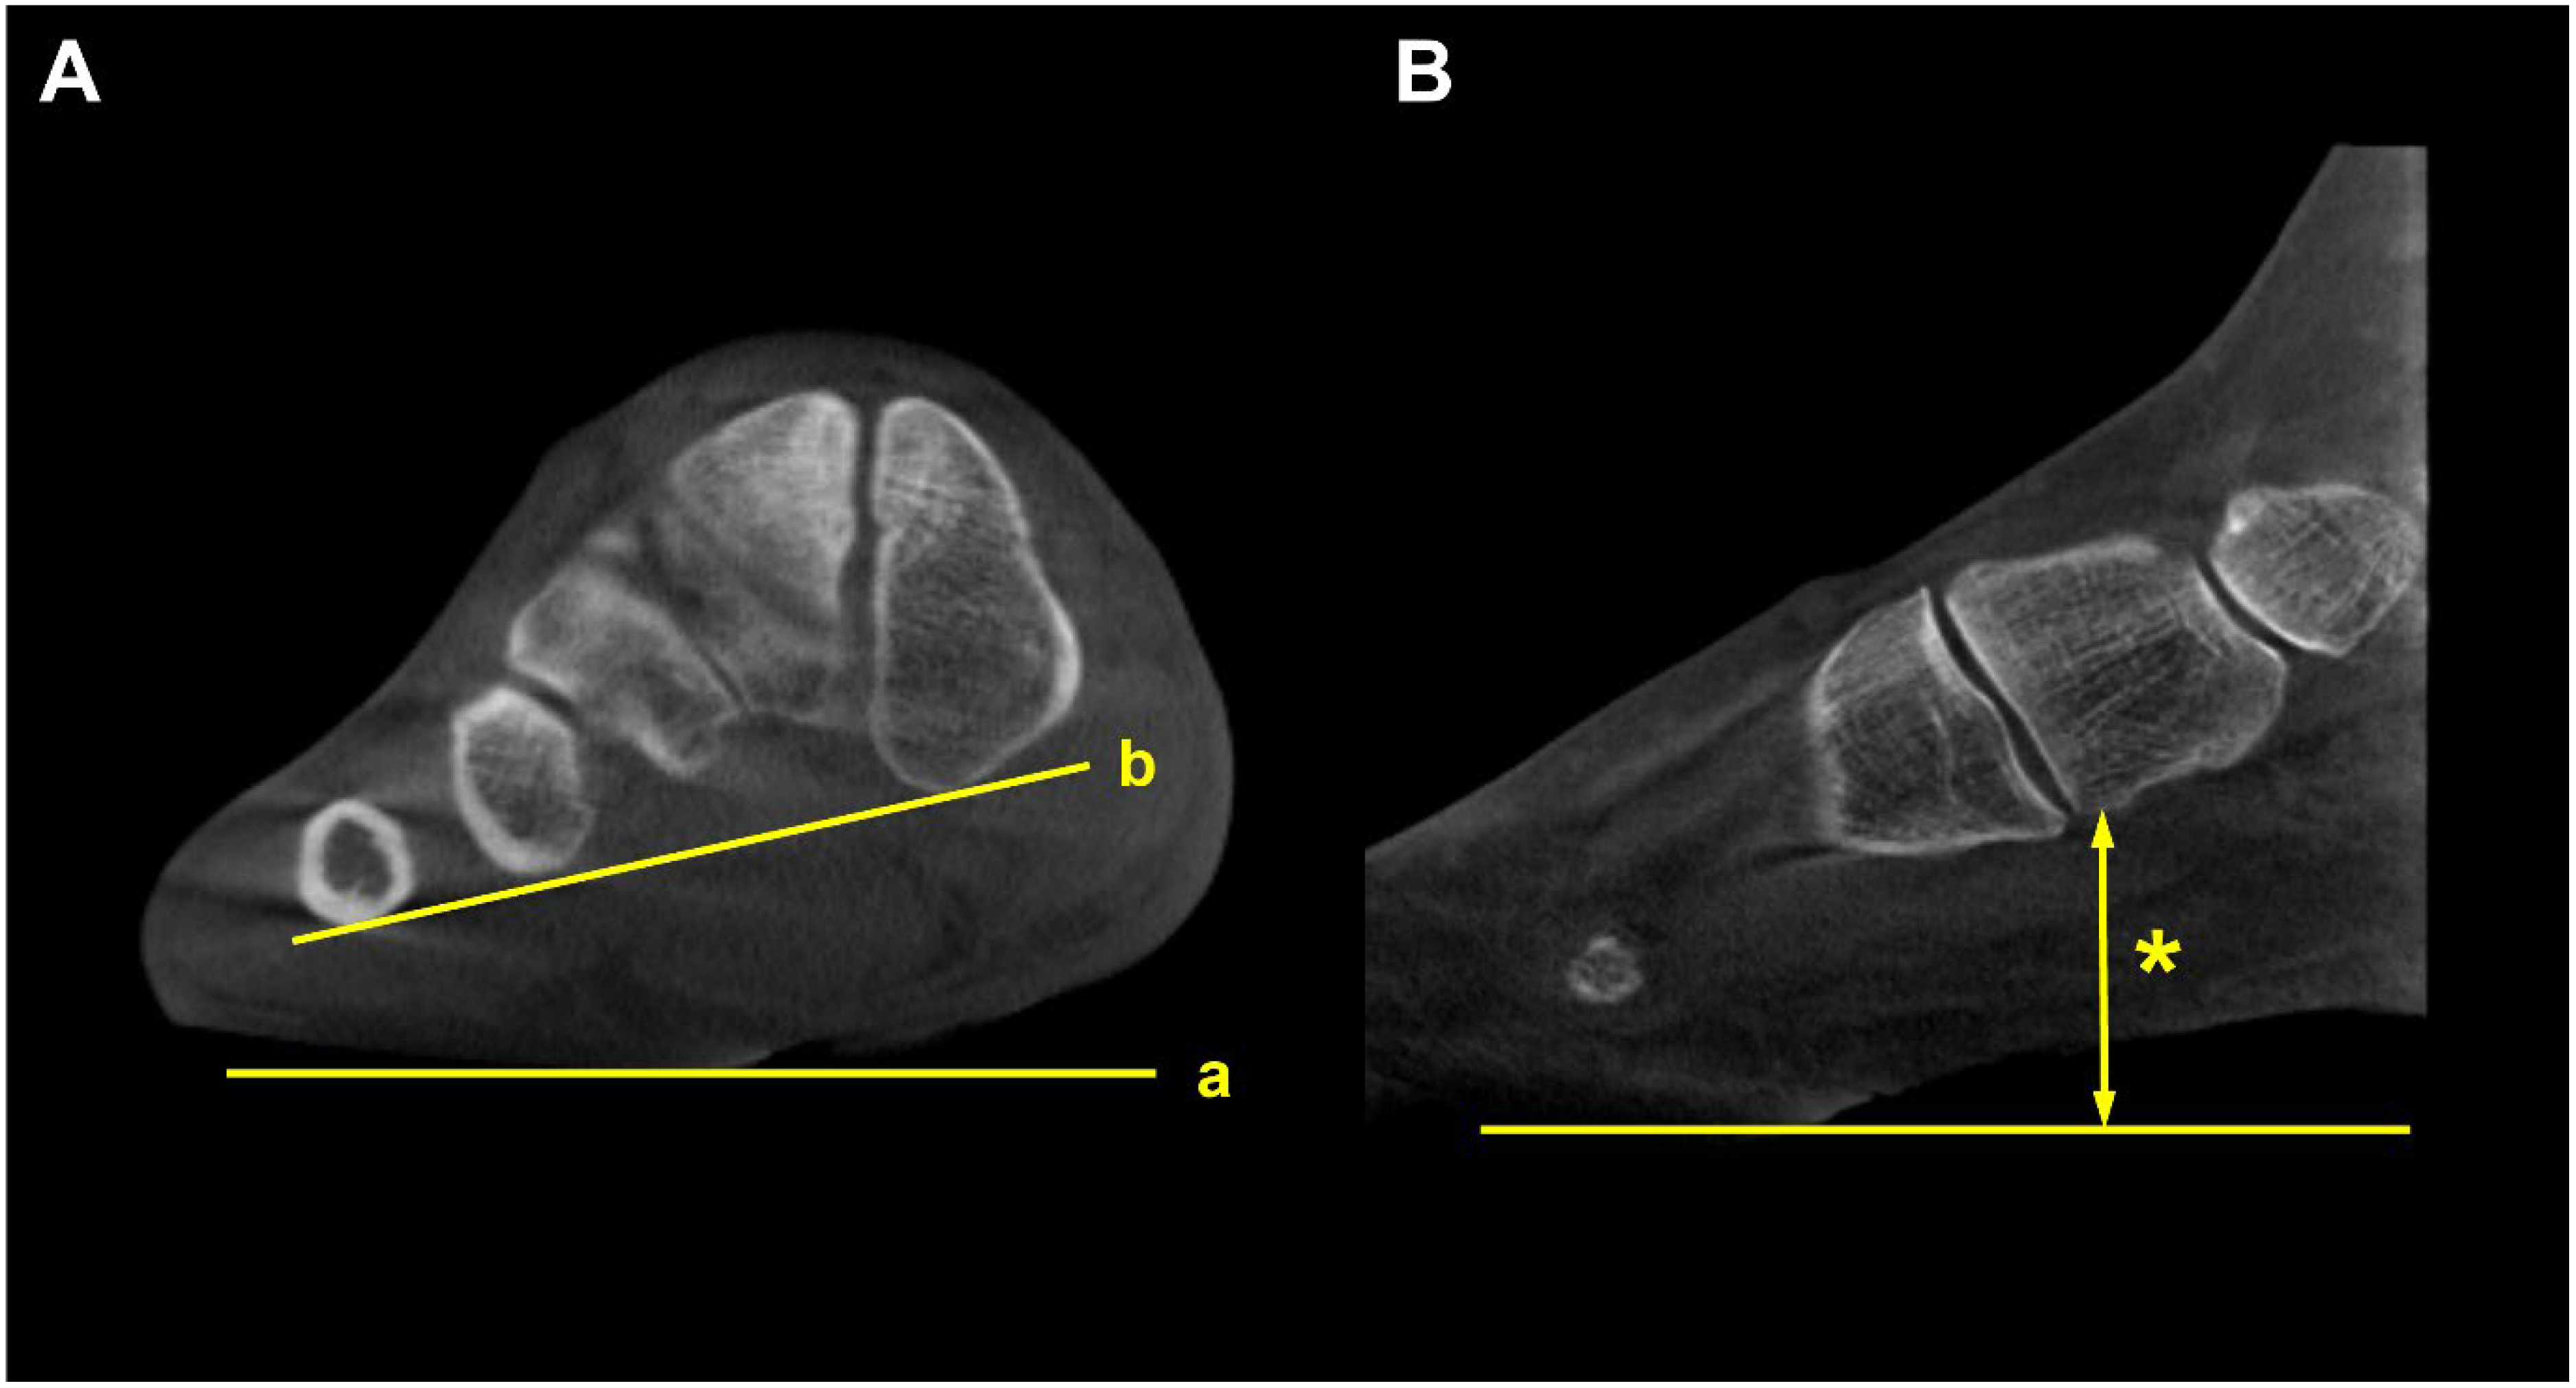

4.3. Medial Column Instability (Class C)

Forefoot arch angle (FAA) and medial cuneiform-to-floor distance (MCFD) are the measurements used to evaluate medial column instability in PCFD [36]. FFA is determined in the coronal plane by establishing a line from the most plantar aspect of the medial cuneiform to the fifth metatarsal. The angle between this line and the ground is defined as FAA. MCFD is measured in the sagittal plane from the most plantar aspect of the medial cuneiform to the ground plate (Figure 10). de Cessar Netto et al. reported that both FAA and MCFD reflect medial column instability with almost perfect reliability [36]. In non-weight-bearing and weight-bearing CT scans, the MCFD measured 29 mm and 18 mm, respectively, and the FFA measured 13 degrees and 3 degrees, respectively, indicating medial column instability with differences observed under weight-bearing conditions.

Figure 10.

Forefoot arch angle (FFA) and medial cuneiform-to-floor distance (MCFD). (A) FFA is defined as an angle between the floor (a) and the line connecting the most plantar aspect of the medial cuneiform and 5th metatarsal (b). (B) MCFD is measured from the most plantar aspect of the medial cuneiform to the floor (asterisk).